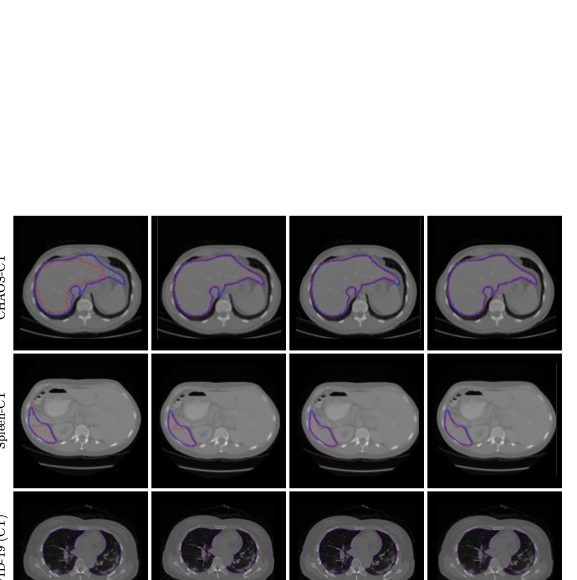

📊 논문 시각자료 (Figures)

Figure 1

Figure 2

Figure 3

Figure 4

Figure 5

Figure 6

Figure 7

Figure 8

Figure 9

Figure 10